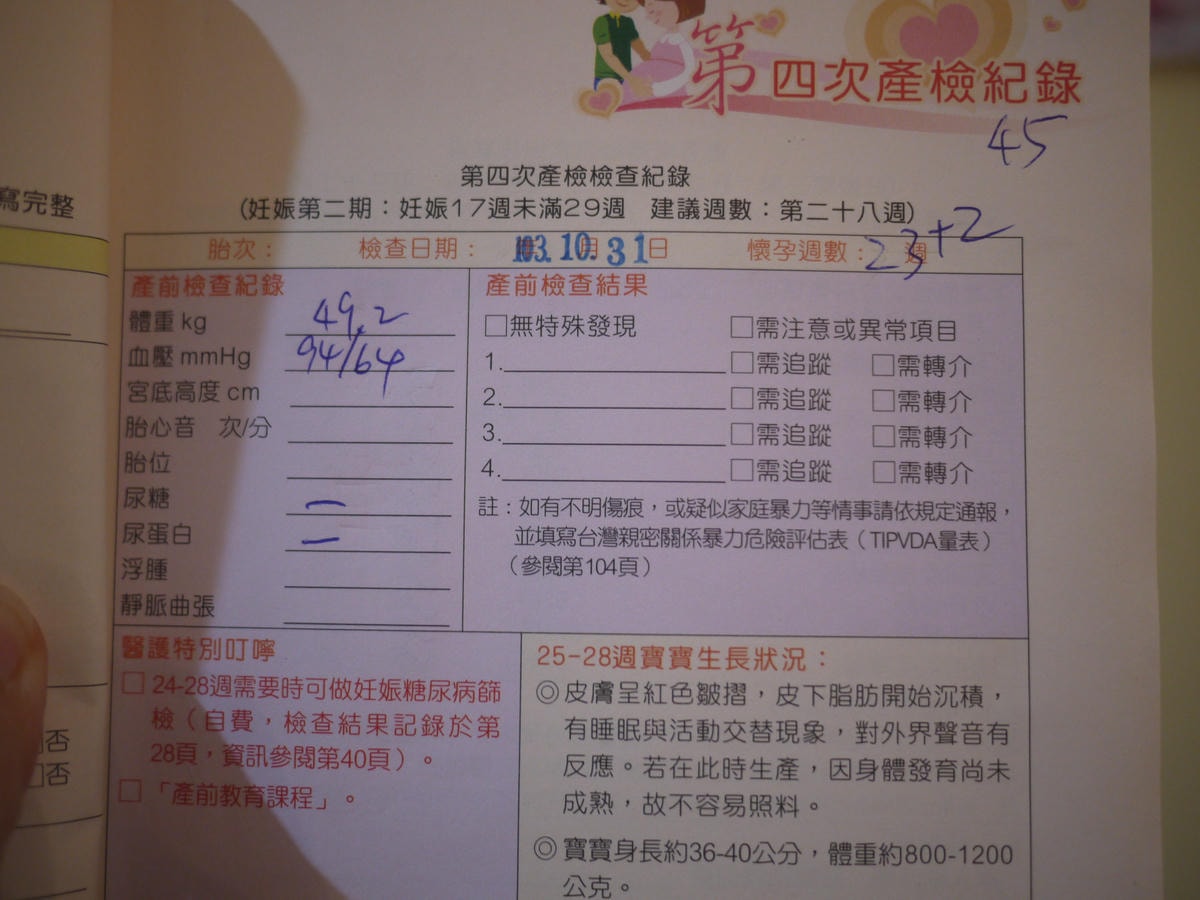

只是現在的體重竟是以前懷芊芊時6個月的體重

(明明現在才三個月就50kg,之前懷芊芊快24週才49.2kg)

現在才三個多月,整個身材卻變得好腫